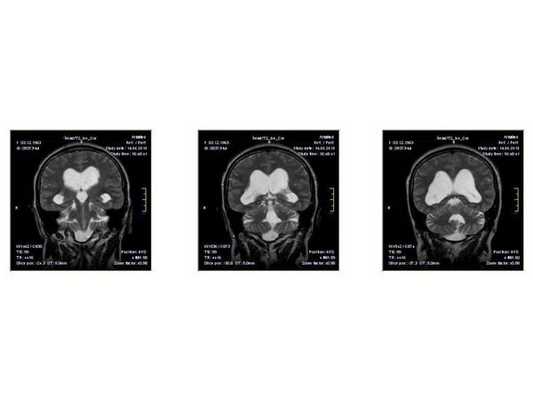

По заключению МРТ от 14.05.2013, после операции в левом полушарии мозжечка появились кистозно-глиозные изменения (на месте повреждённых нейронов образовались рубцовая ткань), а также выраженная внутренняя асимметричная гидроцефалия (избыточное скопление спинномозговой жидкости в полости черепа).

- МРТ в динамике показывает постепенное сужение желудочковой системы на 2 мм. Для сравнения представлены снимки МРТ от 14.05.2013 и от 16.10.2014.